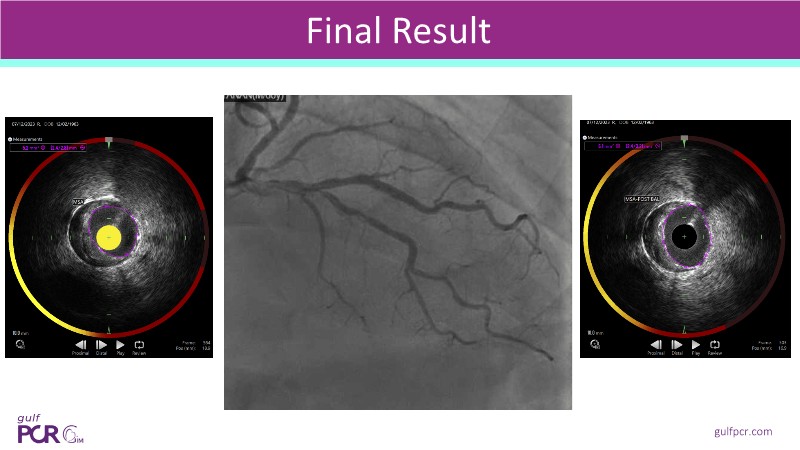

This session explores how near-infrared spectroscopy (NIRS) is redefining PCI by revealing what angiography cannot see. By identifying lipid-rich and vulnerable plaques, NIRS helps anticipate procedural risk and refine decision-making before stent implantation. The session shows how plaque composition, rather than calcium alone, can guide lesion preparation strategies, support safer stent positioning, and improve expansion. Through practical examples, it highlights how integrating NIRS with intravascular imaging and physiology moves PCI toward a more targeted, data-driven, and truly precision-based approach.

- To improve stent placement and expansion: NIRS-IVUS guidance ensures stents are deployed in stable segments, avoiding lipid-rich or heavily calcified areas that may compromise expansion or healing